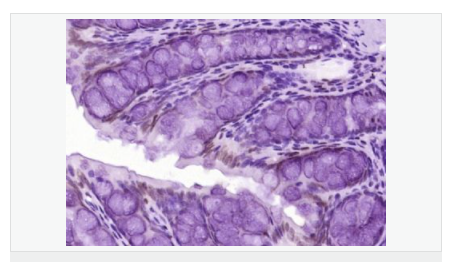

交叉反應(yīng):Human,Mouse,Rat(predicted:Dog,Pig,Cow,Rabbit,Sheep) 推薦應(yīng)用:WB,IHC-P,IHC-F,ICC,IF,ELISA

產(chǎn)品應(yīng)用WB=1:500-2000 ELISA=1:5000-10000 IHC-P=1:100-500 IHC-F=1:100-500 ICC=1:100-500 IF=1:100-500 (石蠟切片需做抗原修復(fù))